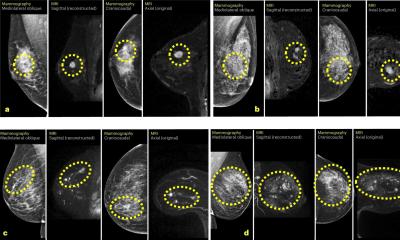

About 60% women in Europe enrolled in a national breast cancer screening programme who have a screening mammogram can feel reasonably confident that radiologists will be able to diagnose early-stage breast cancer. But what about the 30% categorised as having dense breasts, and the10% who have extremely dense breasts? At the 2025 SBI (Society of Breast Imaging) Breast Imaging Symposium held in Colorado Springs, USA, Prof. Ruud Pijnappel, MD, PhD, discussed current clinical trials addressing breast screening of dense-breasted women.Read More